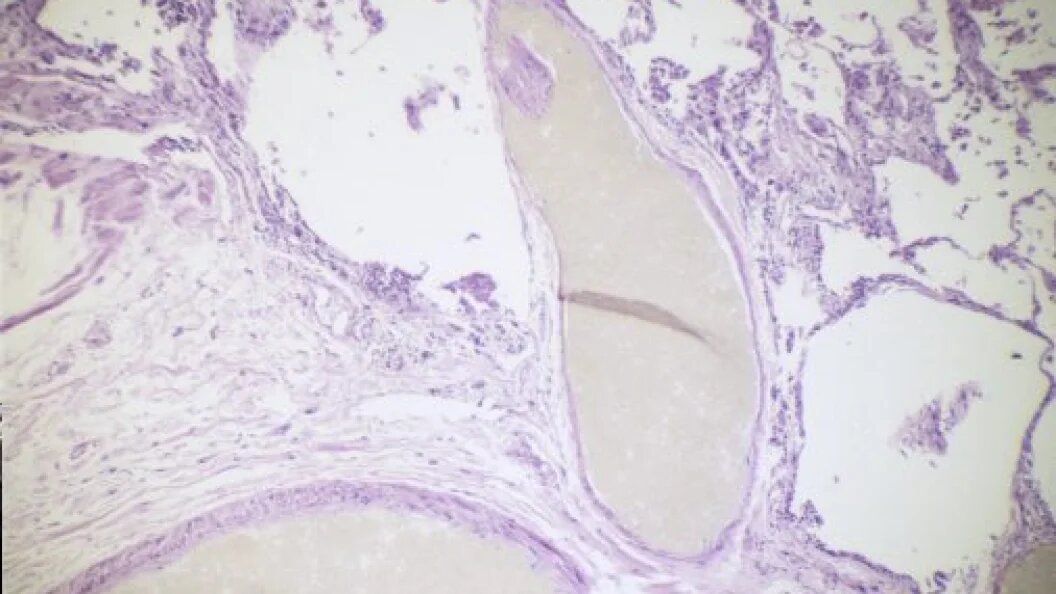

© Custom Medical Stock Photo/Globallookpress

Муковисцидоз является редким генетическим заболеванием, при котором нарушается функционирование экзокринных желез, что приводит к нарушениям в системах дыхания и пищеварения. Прогноз в большинстве случаев неблагоприятный: в европейских странах продолжительность жизни пациентов до 40 лет, в России - преимущественно до 30 лет. В любом случае заболевание тяжелейшее и не поддающееся лечению. Можно лишь поддерживать жизнь пациента.